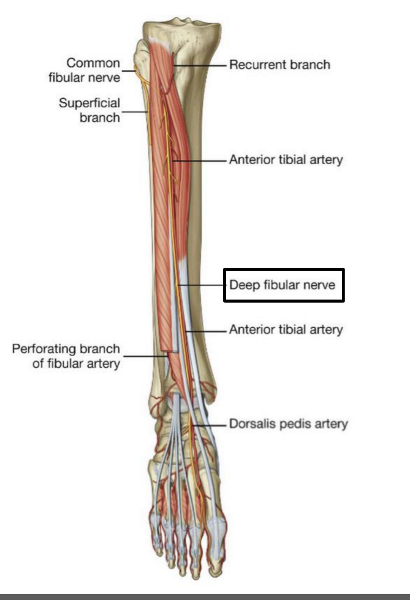

The common fibular nerve is formed from ventral rami from spinal cord levels _______

L4 - S2

The common fibular nerve is the (lateral/medial) division of the sciatic nerve

lateral

Describe the pathway of the common fibular nerve

wraps around the neck of the fibula

bifurcates into deep and superficial fibular nerves

What muscle does the common fibular division of sciatic nerve innervate?

ONLY biceps femoris short head

The superficial fibular nerve is the (lateral/medial) branch of the ________

lateral; common fibular nerve

which muscles does the superficial fibular nerve innervate?

both lateral leg muscles (fibularis longus and fibularis brevis)

The deep fibular nerve is the (medial/lateral) division of the _________-

medial; common fibular nerve

What is the path of the deep fibular nerve?

travels between tibialis anterior and extensor hallucis longus

continues onto the dorsum of the foot for sensory innervation in the flip flop area

Which muscles does the deep fibular nerve innervate?

innervates all anterior leg muscles (extensor hallucis longus, extensor digitorum longus, tibialis anterior, and fibularis tertius) and both muscles of the dorsum of the foot (extensor digitorum brevis, extensor hallucis brevis)

O C D of common fibular nerve

O sciatic nerve

C forms as sciatic nerve bifurcates at apex of popliteal fossa. follows medial border of biceps femoris with its tendon. passes over posterior aspect of head of fibula then winds around neck of fibula deep into fibularis longus where it divides into deep and superficial fibular nerves

D knee joint via articular branch and lateral aspect of posterior leg via sural cutaneous nerve

(common fibular branch of sciatic nerve innervates short head of biceps femoris)

OCD of superficial fibular nerve

O common fibular nerve

C arises between fibularis longus and neck of fibula. descends into lateral compartment of leg; pierces deep fascia at distal third of leg to become subcutaneous

D fibularis longus and brevis. medial dorsal cutaneous n, intermediate dorsal cutaneous n

OCD of deep fibular nerve

O common fibular nerve

C arises between fibularis longus and neck of fibula; passes through extensor digitorum longus and descends on interosseous membrane. crosses distal end of tibia and enters dorsum of foot.

D tibialis anterior, extensors digitorum brevis and longus, extensor hallucis brevis and longus, and fibularis tertius. lateral cutaneous of big toes, medial cutaneous of second toe.